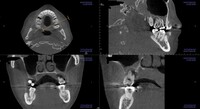

歯科治療の恐ろしさは、少しでも手を抜くと、積み重ねてきた治療効果が全て0=ゼロになってしまうことです。当院では一つ一つの治療過程にベストを尽くすべく、開業当初よりマイクロスコープ、セファロ分析や口腔内スキャンなど最新の機材を取り揃えて、幅広く、深い治療を追求してきました。

私はこれまでの歯科医師人生で、虫歯や歯周病、歯の根にある神経の処置である根管治療、入れ歯、インプラント、美容診療など、幅広く取り組んでまいりました。例えば虫歯治療では、痛みのある歯だけでなく、噛み合わせなどお口の中を総合的に考えたアドバイスや立案をし、歯を長持ちさせる処置を提供することを心がけています。